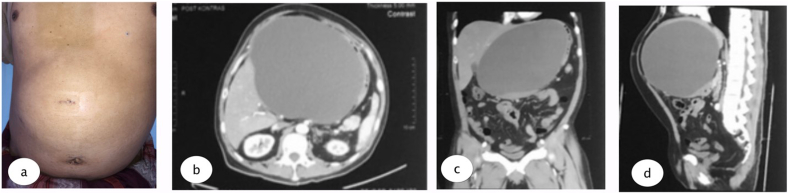

The physical examination found mild jaundice and a spongy mass in the epigastric area. Laboratory examination was conducted with the results: Hb 15.6, Leukocyte 8.76, Total Bilirubin 1.5, direct bilirubin 0.86, SGOT 103, and SGPT 427. A large epigastric cystic mass, without signs of CBD injury could be seen in the Magnetic Resonance Cholangiopancreatography (MRCP). The patient underwent multi slice computed tomography (MSCT) which revealed a cystic mass in the patient’s epigastrium, without discontinuity in CBD (see Fig. 1, Fig. 2, Fig. 3, Fig. 4).

Percutaneous drainage was performed under local anesthesia using 16 FR nasogastric tube (NGT) guided with 5 mm laparoscopic trocar to the most prominent area which could be done in outpatient clinic, and the tube connected to reservoir bag to collect the product. Due to its size we inserted the tube guided from the MSCT results. Evaluation was done every week of the drain product and gradually it reduced after 2 months until the product was negative and the drain could be removed. Results from MSCT evaluation were favorable.

Our patient underwent MRCP that found a large epigastric cystic mass full of leaking bile, without any signs of CBD injury. Abdominal imaging, such as abdominal ultrasound (US), multi-slice computed tomography (MSCT), magnetic resonance cholangiopancreatography (MRCP), and Chole-scintigraphy using 99mTc hepatobiliary iminodiacetic acid (HIDA) scan, are crucial to identify biloma and rule out other possible etiologies [ref. 10]. Ultrasound (US) is preferable as the first-level imaging method, since it is non-invasive, fast and easy to perform. US findings suggest biloma are a hypo-anechoic fluid collection, with well-defined margins, sometimes encapsulated, mono- or pluriconcamerate appearance, in a typical location (right upper abdominal quadrant: sub- or intrahepatic, below the diaphragm) and no vascularity on color Doppler US. The size of a biloma may vary from a few centimeters up to 40 cm in diameter. But the sensitivity of abdominal US is low (70%), though it is used as the initial imaging in the evaluation of biloma. The sensitivity and specificity of CT scan are approximately 90% and those of MRI are above 95% in the detection of biloma and bile leak; however, smaller bilomas can be missed [ref. 4,ref. 10]. The MRCP sequences are helpful to identify the source of the biliary leak. Specifically, thin-slab MRCP sequences may show the point of communication between the fluid collection and bile ducts. Thin-slab MRCP sequences are also helpful in depicting the detailed anatomy of the biliary system and in detecting accessory biliary ducts, which could potentially be the source of the bile leak [ref. 9,ref. 11].

Our patient after 2 months follow-up has no complaints, and when the abdominal lump was gone, then tube could be removed. The patient was evaluated with MSCT showing the biloma was diminished with favorable outcome from the percutaneous drainage. The solution to resolving this complication is early diagnosis and percutaneous drainage under CT guidance. The current body of knowledge is still small, and further research is required to recognize risk factors and prevent future biloma occurrence, reducing morbidity and mortality of the patients.